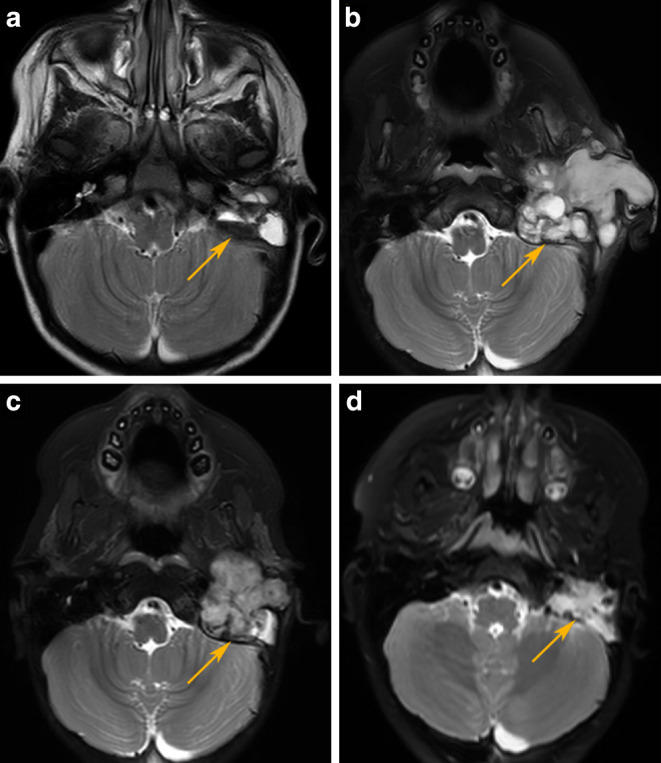

Methods: In our case report, we present a 17-month-old girl with malignant myopericytoma who was successfully treated using CyberKnife (Accuray; Sunnyvale, CA, USA) stereotactic radiotherapy.

Results: A rare localization of the tumor caused significant challenges during the course of treatment. Radical surgical resection was not achievable due to the tumor's location in the inner ear; therefore chemotherapy was initially given to the patient. However, due to the fast progression of the tumor during chemotherapy, we decided to use CyberKnife stereotactic radiosurgery (SRS; 5 fractions of 7 Gy) in order to prevent further invasion of the surrounding tissues. During SRS, tumor growth stopped and the tumor then gradually regressed. Since completion of treatment (currently almost 5 years) our patient has been in complete remission without any significant side effects of the radiation therapy.